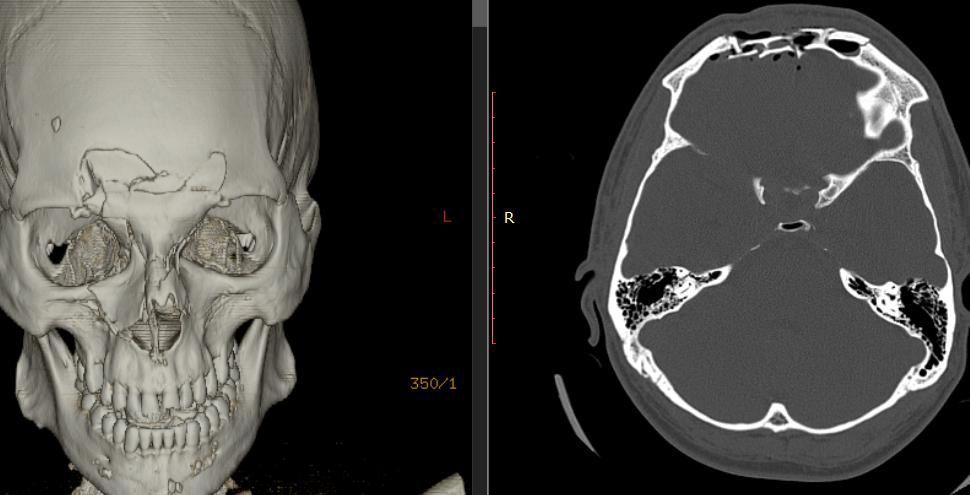

Діагностика

Вдавлений перелом може бути виявлений при хірургічній обробці рани, за допомогою рентгенографії кісток черепа, і краще за все діагностується при виконанні комп’ютерної томографії голови.